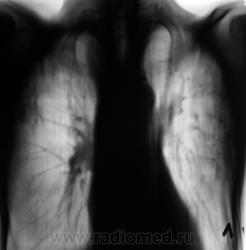

И, уже через год, при плановом обследовании данного пациента, мы "поимели" такие картинки.

А, может быть, не стоит ожидать, когда появится типичный симптом "погремушки". Может, не стоит искусственно выращивать патологию?

Возможно, совершенно по-другому, стоит посмотреть на ранее представленный мною случай?